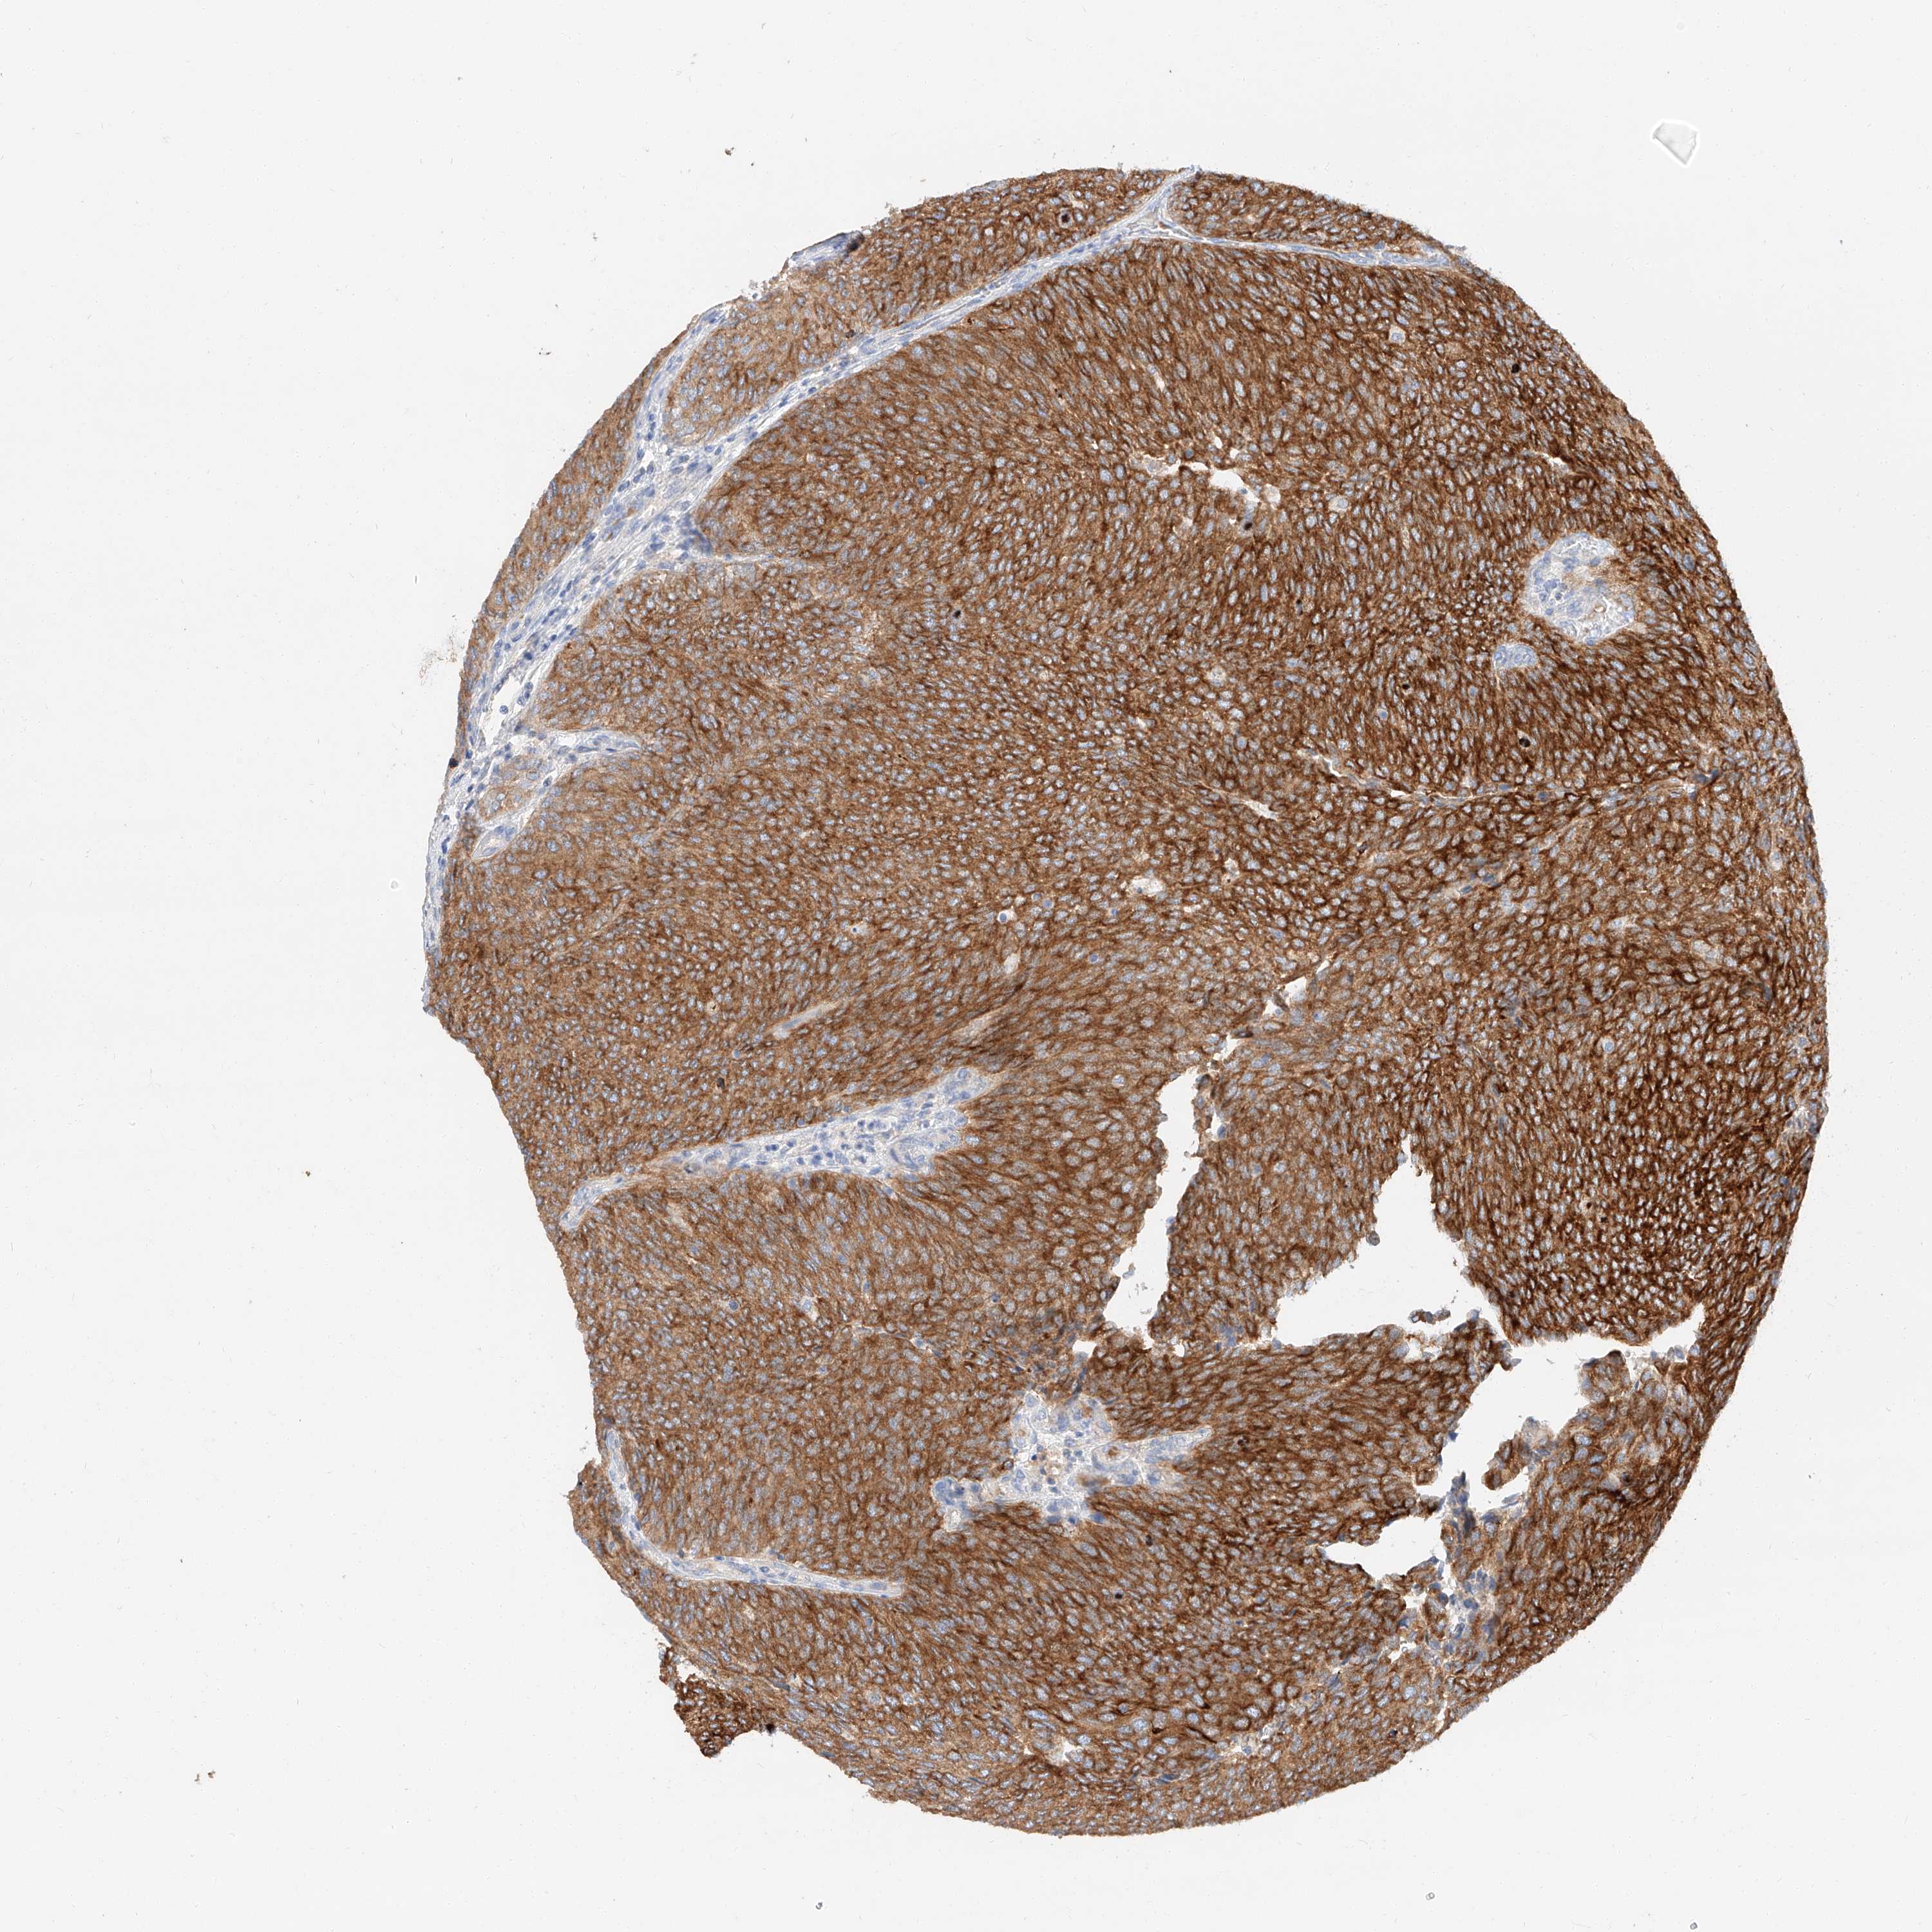

UROTHELIAL CANCER - Protein expressioni

A mouse-over function shows sample information and annotation data. Click on an image to view it in a full screen mode. Samples can be filtered based on level of antibody staining by selecting one or several of the following categories: high, medium, low and not detected. The assay and annotation is described here.

Note that samples used for immunohistochemistry by the Human Protein Atlas do not correspond to samples in the TCGA dataset.

Antibody stainingi

Antibody staining in the annotated cell types in the current human tissue is reported as not detected, low, medium, or high, based on conventional immunohistochemistry profiling in selected tissues. This score is based on the combination of the staining intensity and fraction of stained cells.

Each image is clickable and will lead to virtual microscopy that enables deeper exploration of all samples and also displays staining intensity scores, fraction scores and subcellular localization as well as patient and tissue information for each sample.

Antibody HPA029712

Antibody HPA029713

Staining

High

Medium

Low

Not detected

Intensity

Strong

Moderate

Weak

Negative

Quantity

>75%

75%-25%

<25%

None

Location

Nuclear

Cytoplasmic/membranous

Cytoplasmic/membranous,nuclear

Urothelial carcinoma, High grade